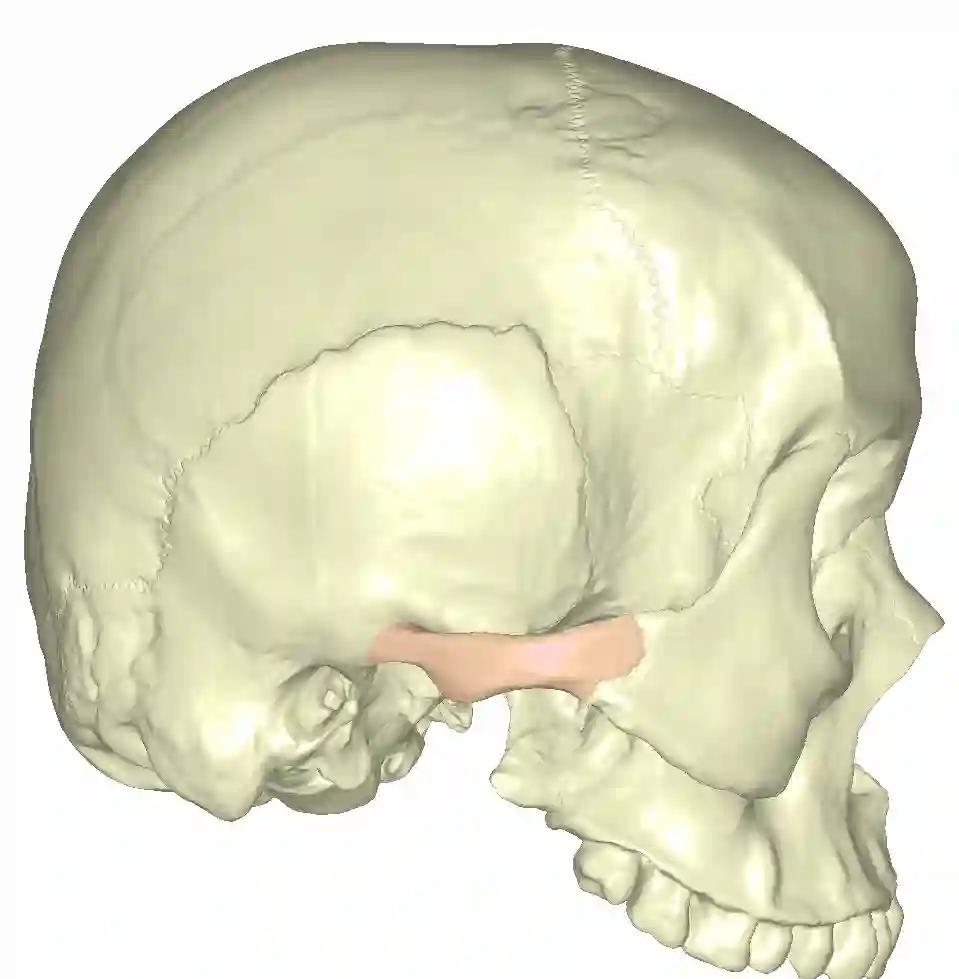

Darstellung des Zygomas in roter Markierung am lateralen Modellschädel.